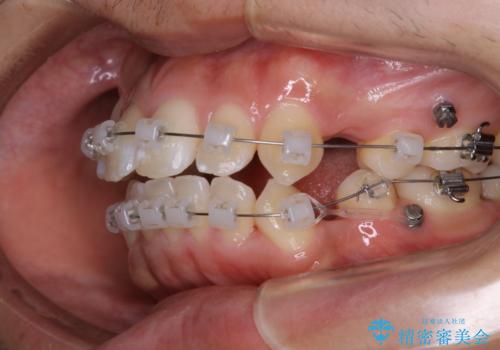

- 矯正装置

- クリア装置

親知らずと、前から4番目の歯を抜歯してワイヤー装置による矯正治療を行いました。

人前に出ることが多いため、当初は目立たない装置をご希望されていましたが、歯の移動距離が大きいため効率よく歯を動かせる表側の装置での治療をお勧めしました。すれ違ってしまっていた奥歯もしっかり治すことができました。